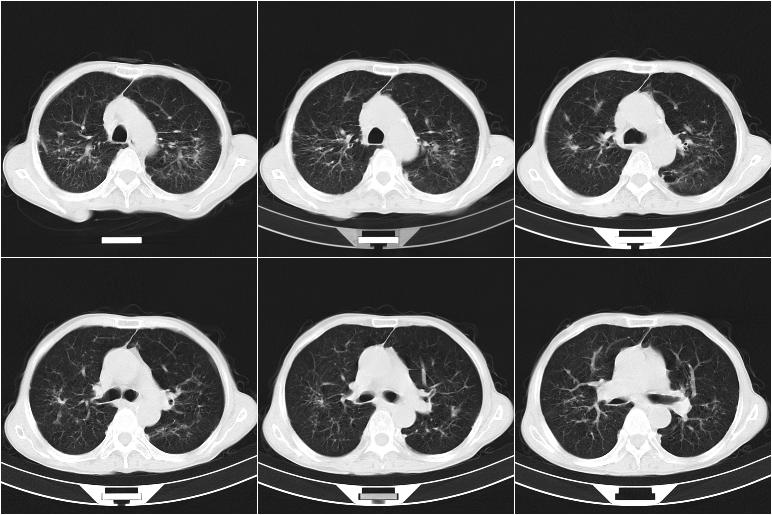

标题: CT21569:M,54Y,右侧中腹部疼痛,IVP示右侧输尿管中下段充盈缺 [打印本页]

标题: CT21569:M,54Y,右侧中腹部疼痛,IVP示右侧输尿管中下段充盈缺

右输尿管下段扩张积水。左下腹部肠管间质瘤不除外。

看不清,应打个增强,右侧输尿管扩张,右侧肠系膜上好像占位。

右侧输尿管扩张.

右侧输尿管扩张积水,考虑结石,最好做个增强除外输尿管占位性病变

右输尿管下段扩张

右侧输尿管扩张积水,最好做个增强除外输尿管占位性病变

右侧输尿管扩张积水,建议增强排除占位。

支持右侧输尿管中下段扩张积水,建议增强排除占位。

右侧输尿管下段扩张,原因待查;建议行进一步检查。

右输尿管下段扩张积水,壁增厚、边缘不光整,考虑炎性改变

ct21569和ct21569b(增强)结果:阑尾腺癌,侵犯回盲部及输尿管中段。手术切除部分升结肠、回肠及受侵4cm之输尿管,做回-横结吻合,输尿管支架置放术并吻合,术后病理腺癌,阑尾来源可能性大。

右侧输尿管扩张似见软组织密度影,输尿管占位不能排除。